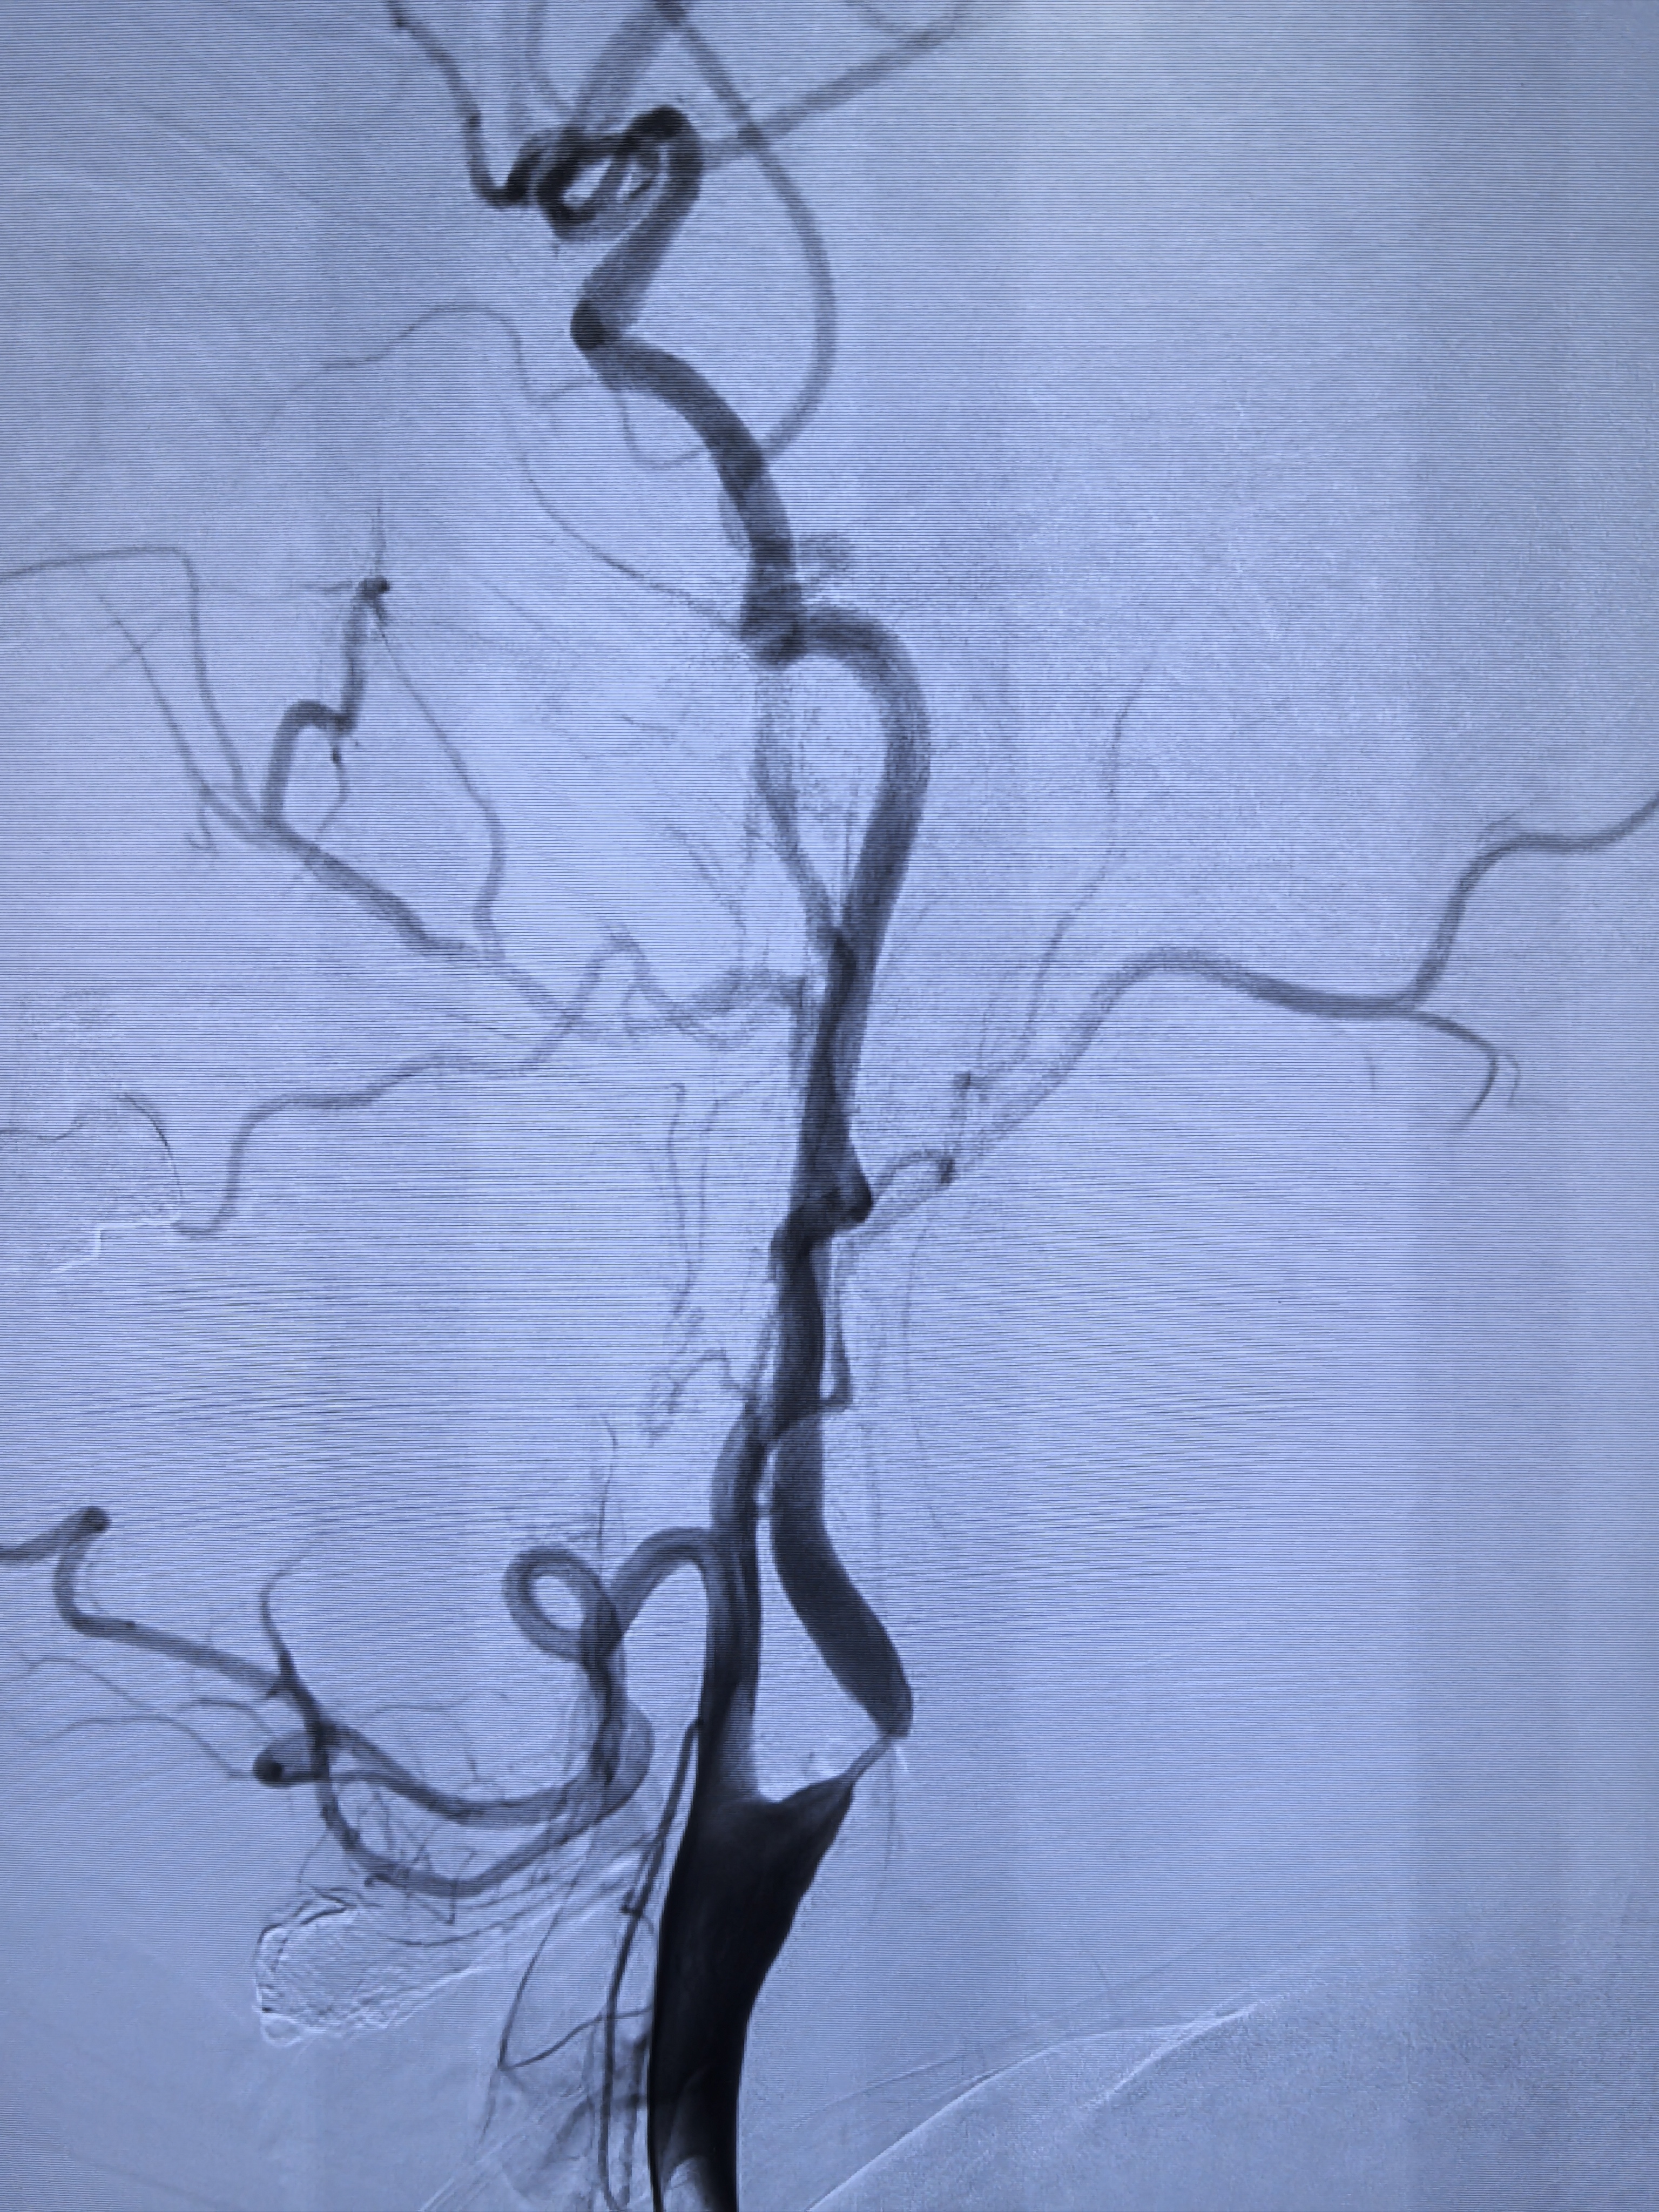

治療前突發(fā)腦梗,外院治療腦梗期間,檢查發(fā)現(xiàn)右側(cè)頸內(nèi)動脈閉塞,左側(cè)頸內(nèi)動脈極重度狹窄。目前言語活動均正常,無嚴重腦梗后遺癥。磁共振檢查見雙側(cè)梗塞后遺改變。治療中造影發(fā)現(xiàn)右側(cè)頸內(nèi)動脈完全閉塞,左側(cè)頸內(nèi)動脈極重度狹窄,接近閉塞。有左側(cè)頸內(nèi)動脈支架植入指征。支架植入后使用5mm球囊后擴張,仍有小部分殘余狹窄,不影響頸內(nèi)動脈血流。治療后治療后即刻支架植入后使用5mm球囊后擴張,仍有小部分殘余狹窄,不影響頸內(nèi)動脈血流。手術(shù)順利恢復良好,左側(cè)大腦血供明顯改善,言語活動均正常,予出院。